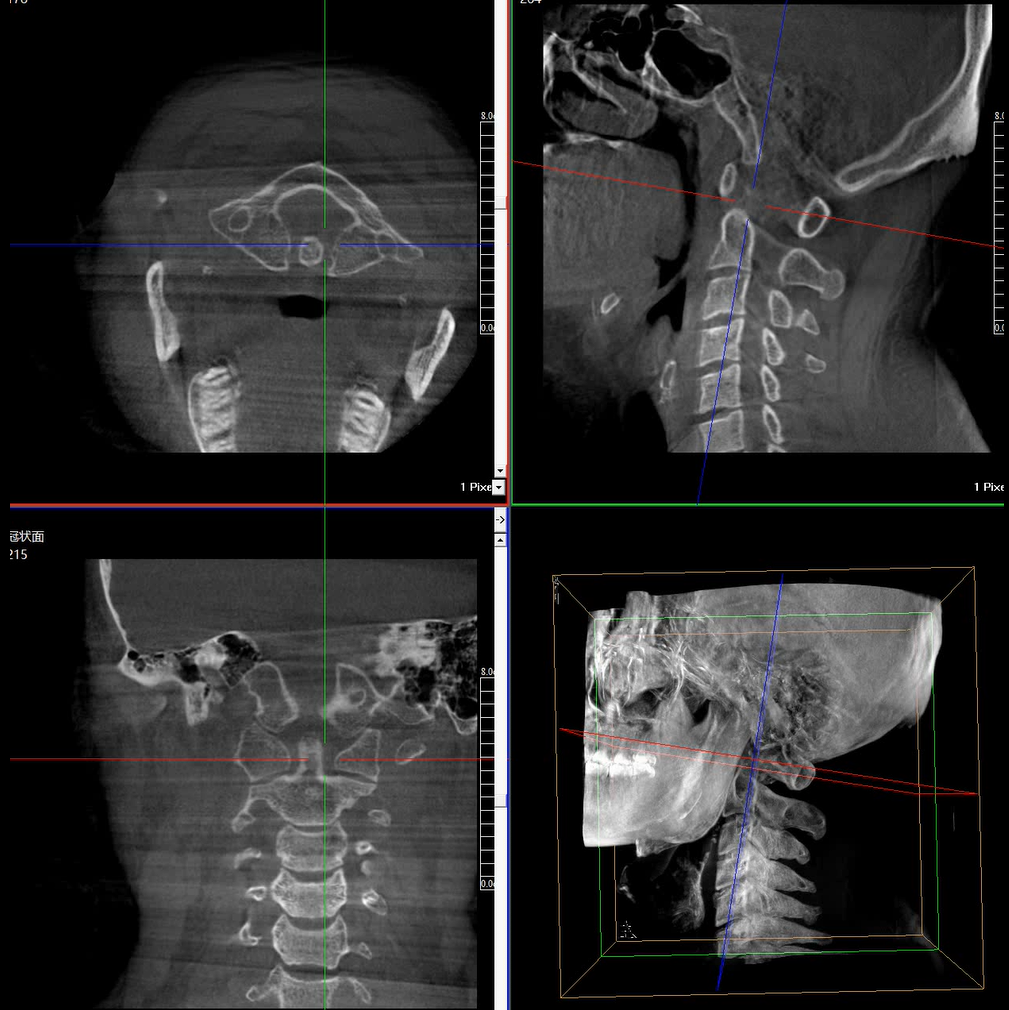

術(shù)中三維成像和橫斷面圖像提供多角度的手術(shù)診斷信息,輔助醫(yī)生進(jìn)行術(shù)中評估判斷,諸如骨折復(fù)位情況和內(nèi)植入螺釘?shù)某叽绾臀恢?,輔助手術(shù)更好地完成。

提供更大的術(shù)中三維成像視野,采集更多圖像信息,可一次拍全全段頸椎、全段腰椎、七節(jié)胸椎、雙側(cè)骶髂關(guān)節(jié)、股骨頭及單側(cè)盆骨。

在C臂掃描過程中,始終保持拍攝主體處于射線束的中心,避免了序列圖像采集過程中的橫縱方向運動,減少相對運動造成的運動偽影。